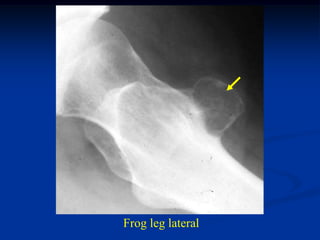

Case #124

11 year male

chondromyxoid fibroma

proximal tibia